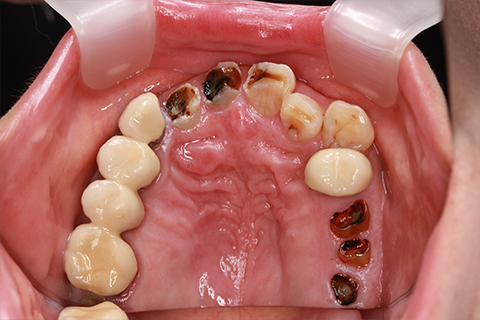

症例5

治療前

インプラント埋入時

治療後

- 年齢・性別

- 35歳男性

- 治療期間

- 3ヶ月

- 抜歯

- 右上1.3左上6.7の残根抜歯

- 治療費

- 123.2万円

- 備考

- 右上1.3左上6.7の欠損部

- 治療内容

- 4本のインプラントを一回のオペで埋入。

- 施術の副作用(リスク)

- オペによる知覚障害。インプラントによる歯肉炎。インプラント脱落。